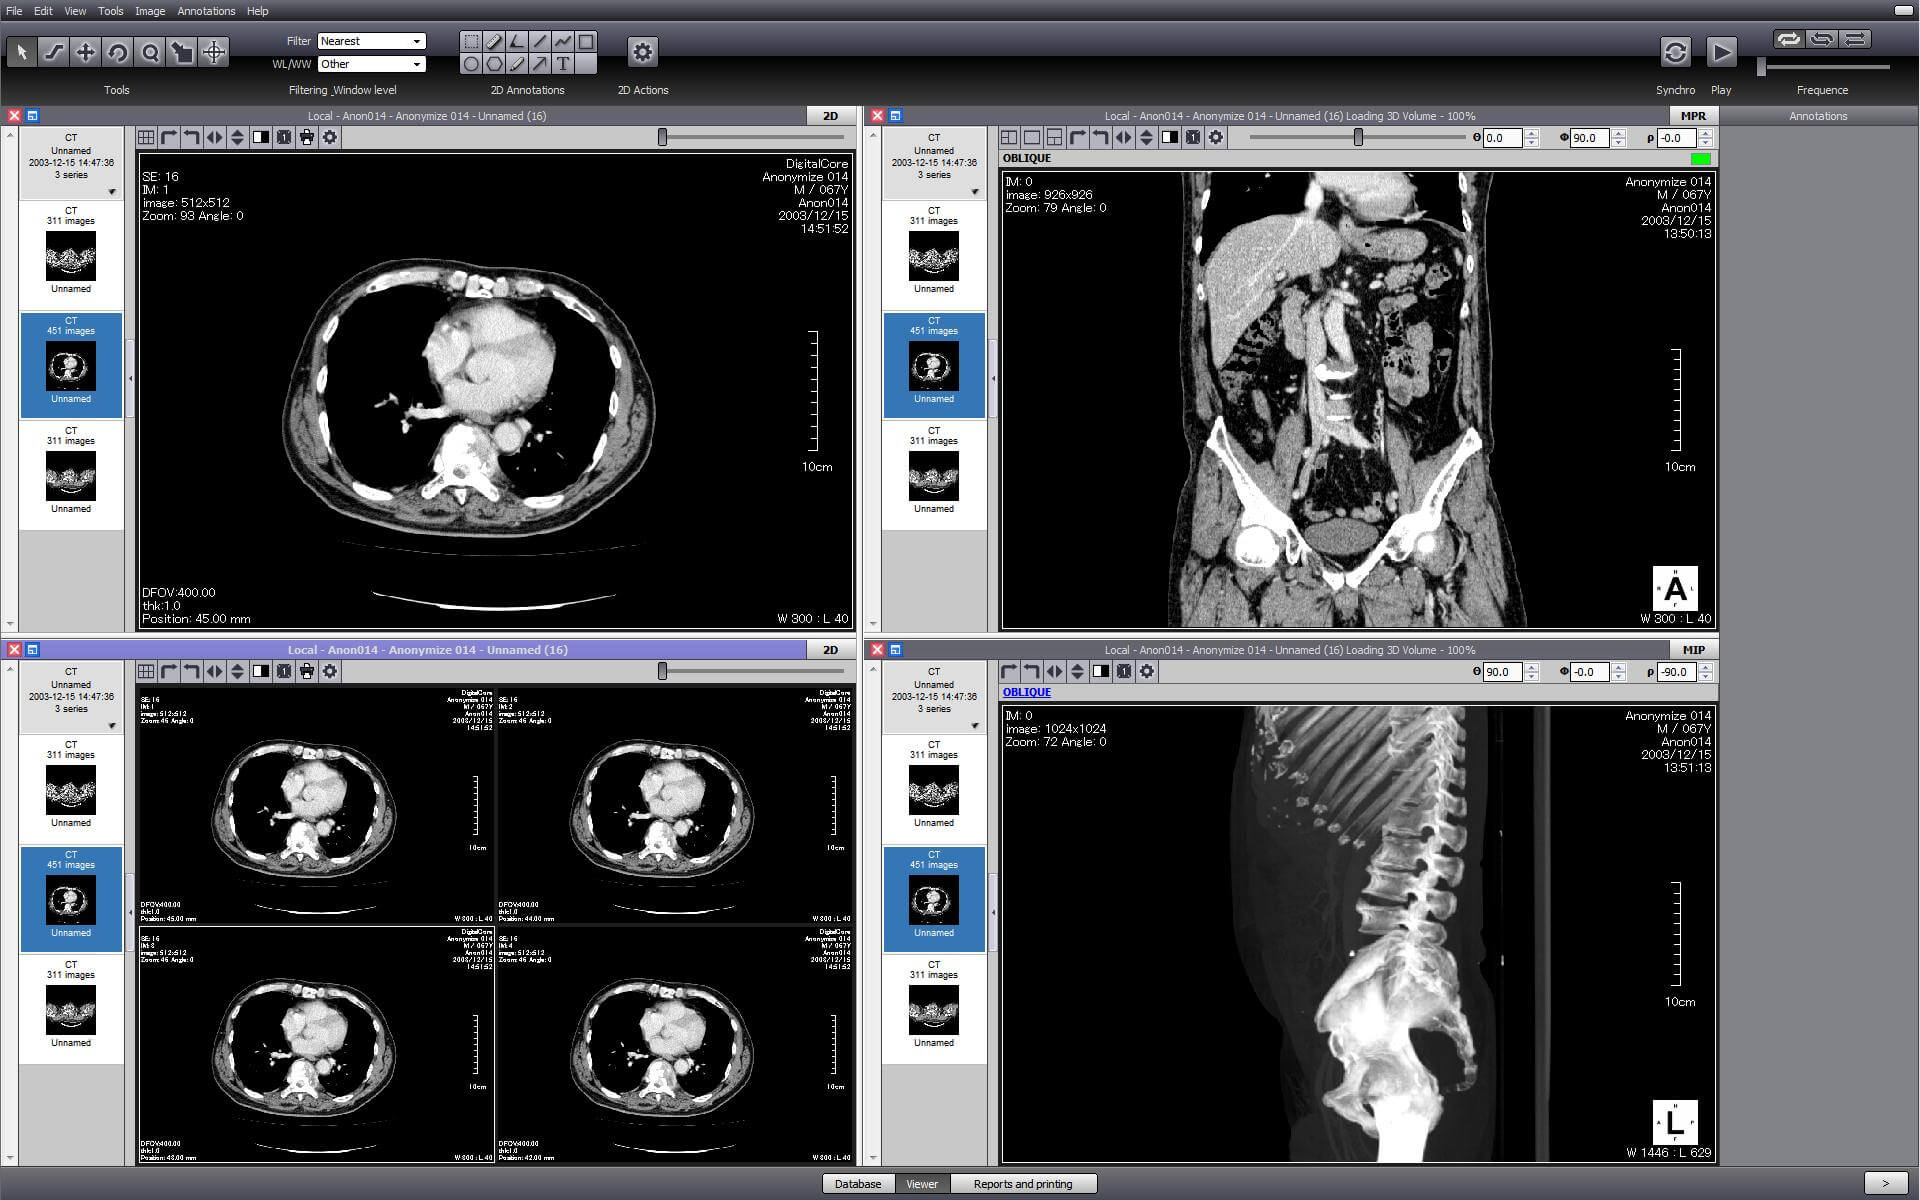

This is one of the few viewers that is compatible with Windows, Mac OS X, and Linux. It is an open source project that supports PACS. It has all the standard DICOM tools, but not many of the advanced tools required in medical diagnosis and research. The Pro version has advanced features like MPR and MIP.